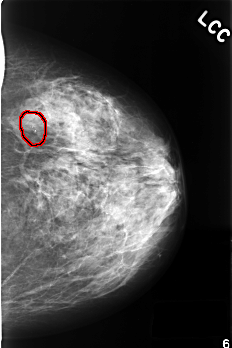

FILE: C_0379_1.LEFT_MLO.OVERLAY TOTAL_ABNORMALITIES 1 ABNORMALITY 1 LESION_TYPE CALCIFICATION TYPE PLEOMORPHIC DISTRIBUTION CLUSTERED ASSESSMENT 4 SUBTLETY 5 PATHOLOGY BENIGN TOTAL_OUTLINES 1 BOUNDARY |

FILE: C_0379_1.LEFT_CC.OVERLAY TOTAL_ABNORMALITIES 1 ABNORMALITY 1 LESION_TYPE CALCIFICATION TYPE PLEOMORPHIC DISTRIBUTION CLUSTERED ASSESSMENT 4 SUBTLETY 5 PATHOLOGY BENIGN TOTAL_OUTLINES 1 BOUNDARY |